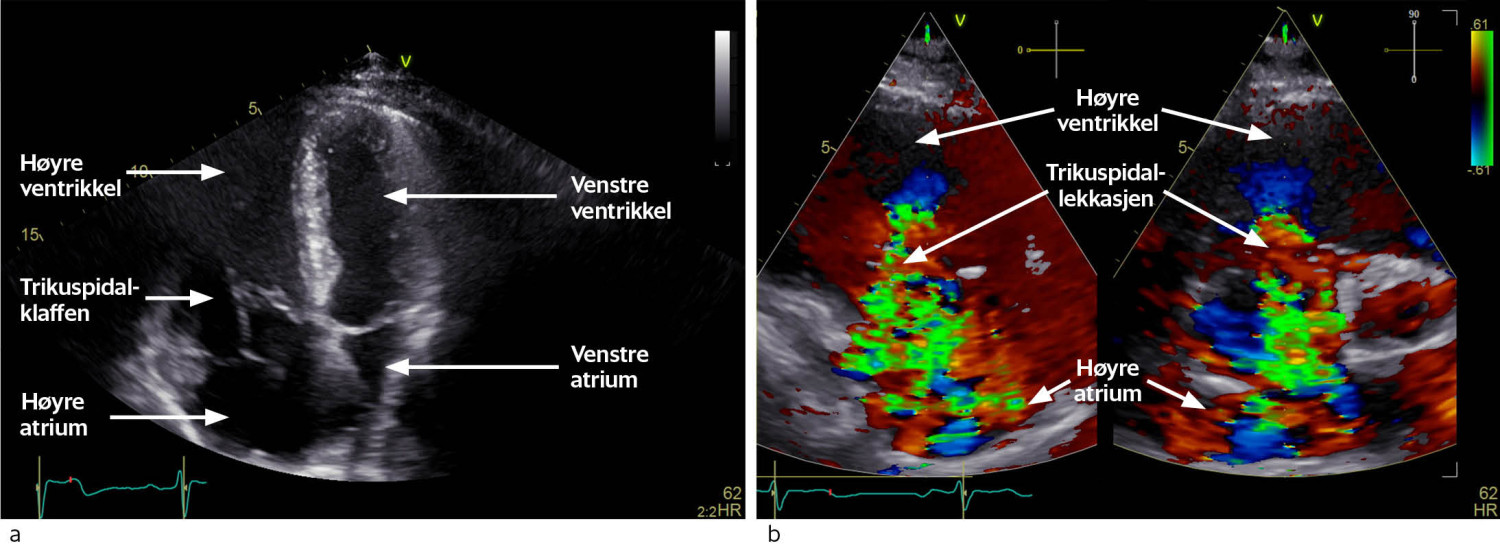

Pasienten kom til hjertemedisinsk utredning ved universitetssykehuset et par måneder senere. Transtorakal og transøsofageal ekkokardiografi bekreftet omfattende trikuspidalpatologi med chordarupturer og prolaps av anteriore segl (figur 1a). Trikuspidalannulus var dilatert, og det var manglende systolisk kontakt mellom klaffeseglene. Dette forårsaket en stor lekkasje (Figur 1b) med systolisk reversering av blodstrøm i levervenene. Vena cava inferior var dilatert og hadde manglende respirasjonsvariasjon, forenlig med høyt høyresidig fylningstrykk. Høyre ventrikkel var dilatert, med normal veggtykkelse og god langaksebevegelse. Høyre atrium var også dilatert. I tillegg hadde pasienten en forholdsvis stor medfødt atrieseptumdefekt i sekundumområdet av atrieseptum (figur 2a og b). Det var ikke ekkokardiografiske holdepunkter for pulmonal hypertensjon.